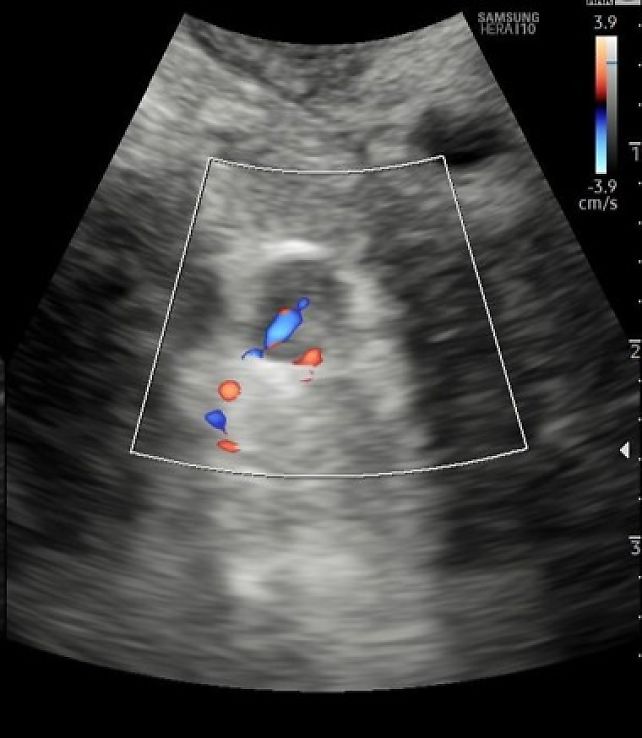

Vascularization (assessed by Doppler imaging)

- Suspicious/malignant nodes

- peripheral or mixed vascularity (Figure 16)

- transcapsular flow (vessels penetrating from the periphery towards the center) suggesting tumor infiltration

- chaotic blood flow on power Doppler

16

Pelvic node with mixed vascularization, visualized with a convex probe.